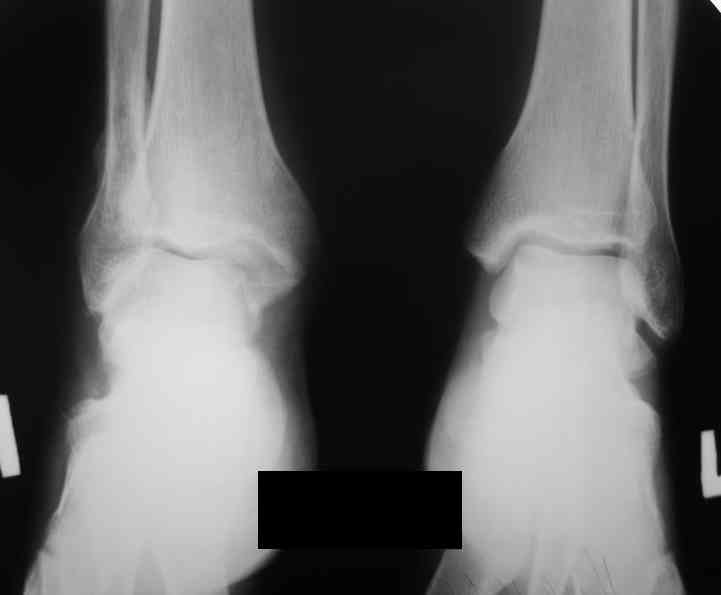

Уважаемые коллеги. Хотелось бы услышать ваше мнение по следующему случаю Обратился больной 23 года, травма 4 месяца назад - закрытый перелом наружной, внутренней лодыжки правой голени. Лечился консервативно, гипсовой иммобилизацией 8 недель, после снятия последней прошел курс восстановительного лечения. Беспокоят боли в области правого голеностопного сустава больше в проекции внутренней лодыжки, к вечеру. Отечность области сустава при физических нагрузках.Походка не изменена. Контуры правого голеностопного сустава сглажены. Имеется вальгусная установка правой пяточной кости. Объем движений в голеностопном суставе подошвенное / тыльное сгибание 50/0/80, безболезненные. Посоветуйте что делать в данной ситуации. Мне видится следующий вариант решения данной деформации: Восстановление нормальной анатомии голеностопного сустава - остеотомия малоберцовой кости и внутренней лодыжки, удалить все рубцы из области дистального межберцового синдесмоза, восстановить длину и устранить ротационное смещения наружной лодыжки.( встанет ли таранная кость на место?), фиксация наружной лодыжки пластиной, внутренней - винтами, дистального межберцового синдесмоза винтом. ЭОПом не располагаем. Что вы посоветуете? Где могут быть - технические трудности, <подводные камни>.

Здесь поаккуратней. Перелом тип В, возможно имеется только частичный разрыв дистальной порции передней тибио-фибулярной связки...и все. "Удалить все рубцы из области дистального межберцового синдесмоза", значит приговорить его к синостозу.

1) непросто определить линию перелома наружной лодыжкию но рубить надо по ней именно потому, что это перелом тип В, связки синдесмоза пострадали минимально. Если сделать остеотомию выше, то для устранения укорочения м\б кости синдесмоз придется разрушать - это не есть хорошо.

План вполне здравый. Но... Такое впечатление, что после устранения подвывиха суставные поверхности уже могут быть неконгруэнтны все равно.

То ли там есть импрессия в наружном отделе суставной площадки tibia, то ли не знаю что... IMHO не сильно криминальым выглядит и вариант